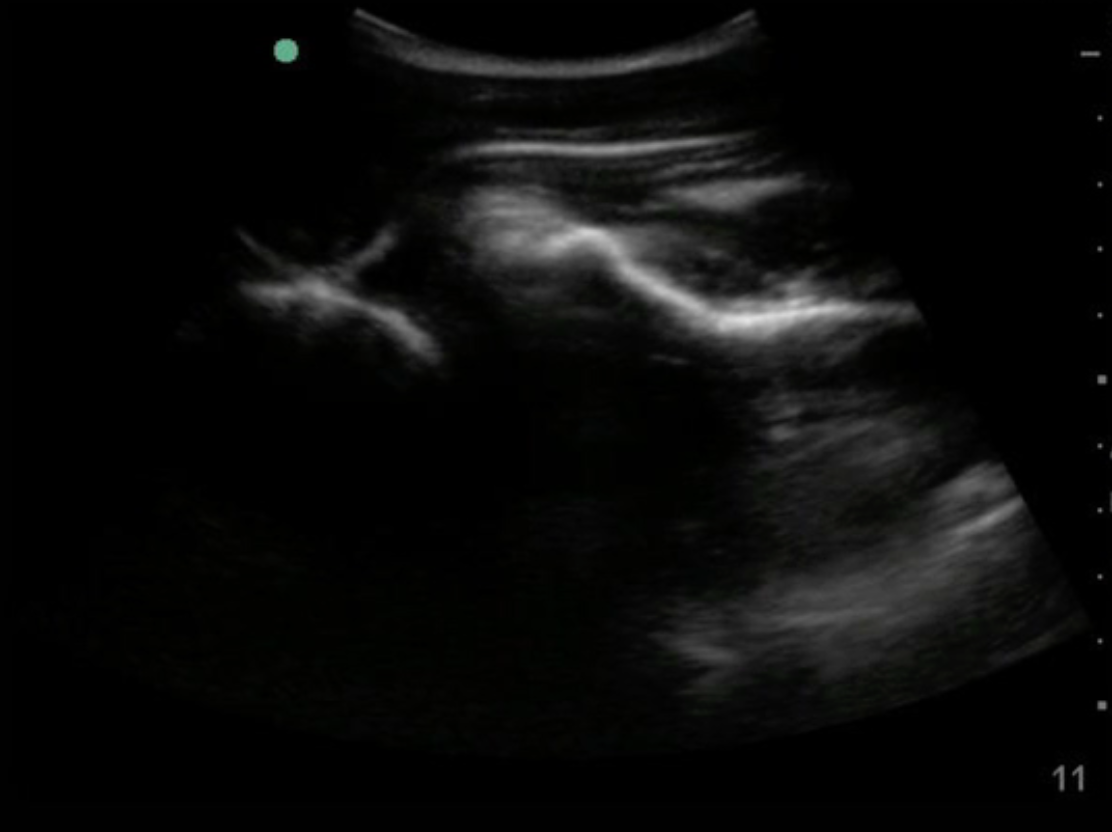

Shoulder Dislocation

Normal

Posterior Approach

- Select curvilinear probe (low freq probe)

- Place probe to the posterior chest parallel above the scapular spine

- Identify the glenoid and humeral head

Anterior Approach

- Place probe to the anterior chest parallel to the glenohumeral joint